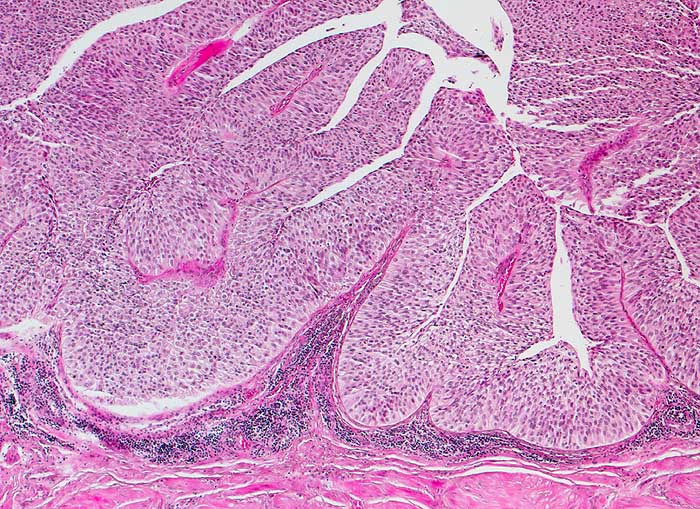

Bei den meisten papillären Urotheltumoren finden sich kleine Büschel von kubischen oder zylindrischen Urothelien. Die Kerne sind leicht vergrössert, oft spindelig und hyperchromatisch. Papilläre Karzinome mit leichter Epitheldysplasie sind aufgrund der sehr geringen Zellatypien in bis zu 50% der Fälle zytologisch nicht diagnostizierbar. Bei mässiger Epitheldysplasie sind die Urothelien polymorpher und hyperchromatischer.

Unten werden Beispiele von einem hoch differenzierten und drei mässig differenzierten papillären Karzinomen gezeigt.